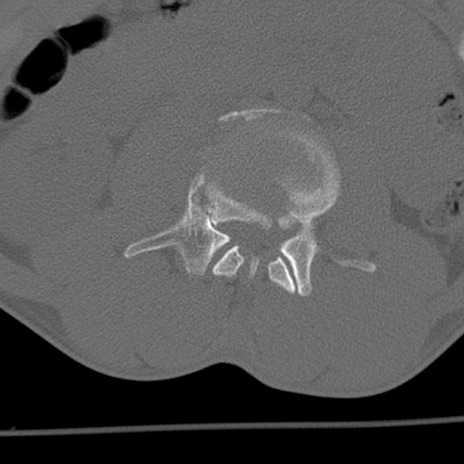

腰椎CT

矢状断像